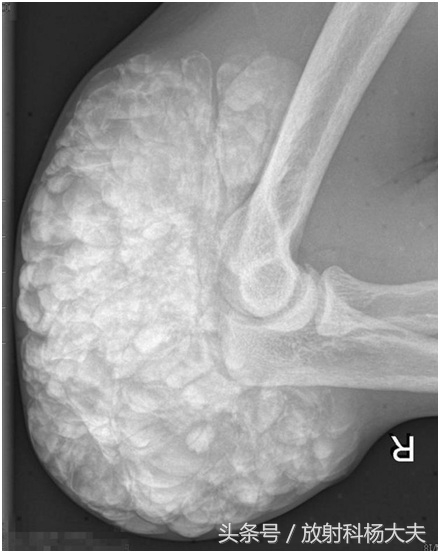

刘叔今年50岁,刘叔是赫赫有名的农村致富能手。12年前发现右侧肘部及前臂皮下多个质软结节,无明显红热痒痛现象,肘关节活动正常,随时间推移,上述结节逐渐增大,后沿尺骨方向逐渐形成成块并影响肘关节活动。刘叔半个月前来我院就诊。骨科专科检查:包块长度约10cm,宽度5.5cm,触之硬韧,边界不清,并轻微压痛。x线片:右肘关节各构成骨未见增生、破坏等骨质异常X线征,右肘关节旁软策划中可见团状阴影,团块由大量大小不一结节状高密影融合而成的。

X线检查是诊断TC的基本方法, 其表现为关节旁关节伸侧软策划中, 呈大小不一的钙化结节集结而成的分叶状团块,呈“卵石样”,“桑葚状”,范围较广者可呈“流注状”;病变一般不累及邻近关节或骨骼。CT与X线平片表现一致,但CT对病变部位、形态及范围的显示更为全面, 能清楚显示病变与邻近关节及骨骼的关系。MRI具有多参数、多序列、多方位成像的功能,可根据信号判断策划成分,。能多方位显示病变不累及关节或骨骼, 对诊断有较大帮助。